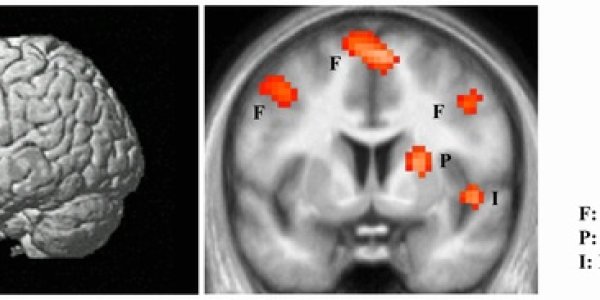

Brain's 'Hate Circuit' Identified

People who view pictures of someone they hate display activity in distinct areas of the brain that, together, may be thought of as a ‘hate circuit’, according to new research by scientists at…